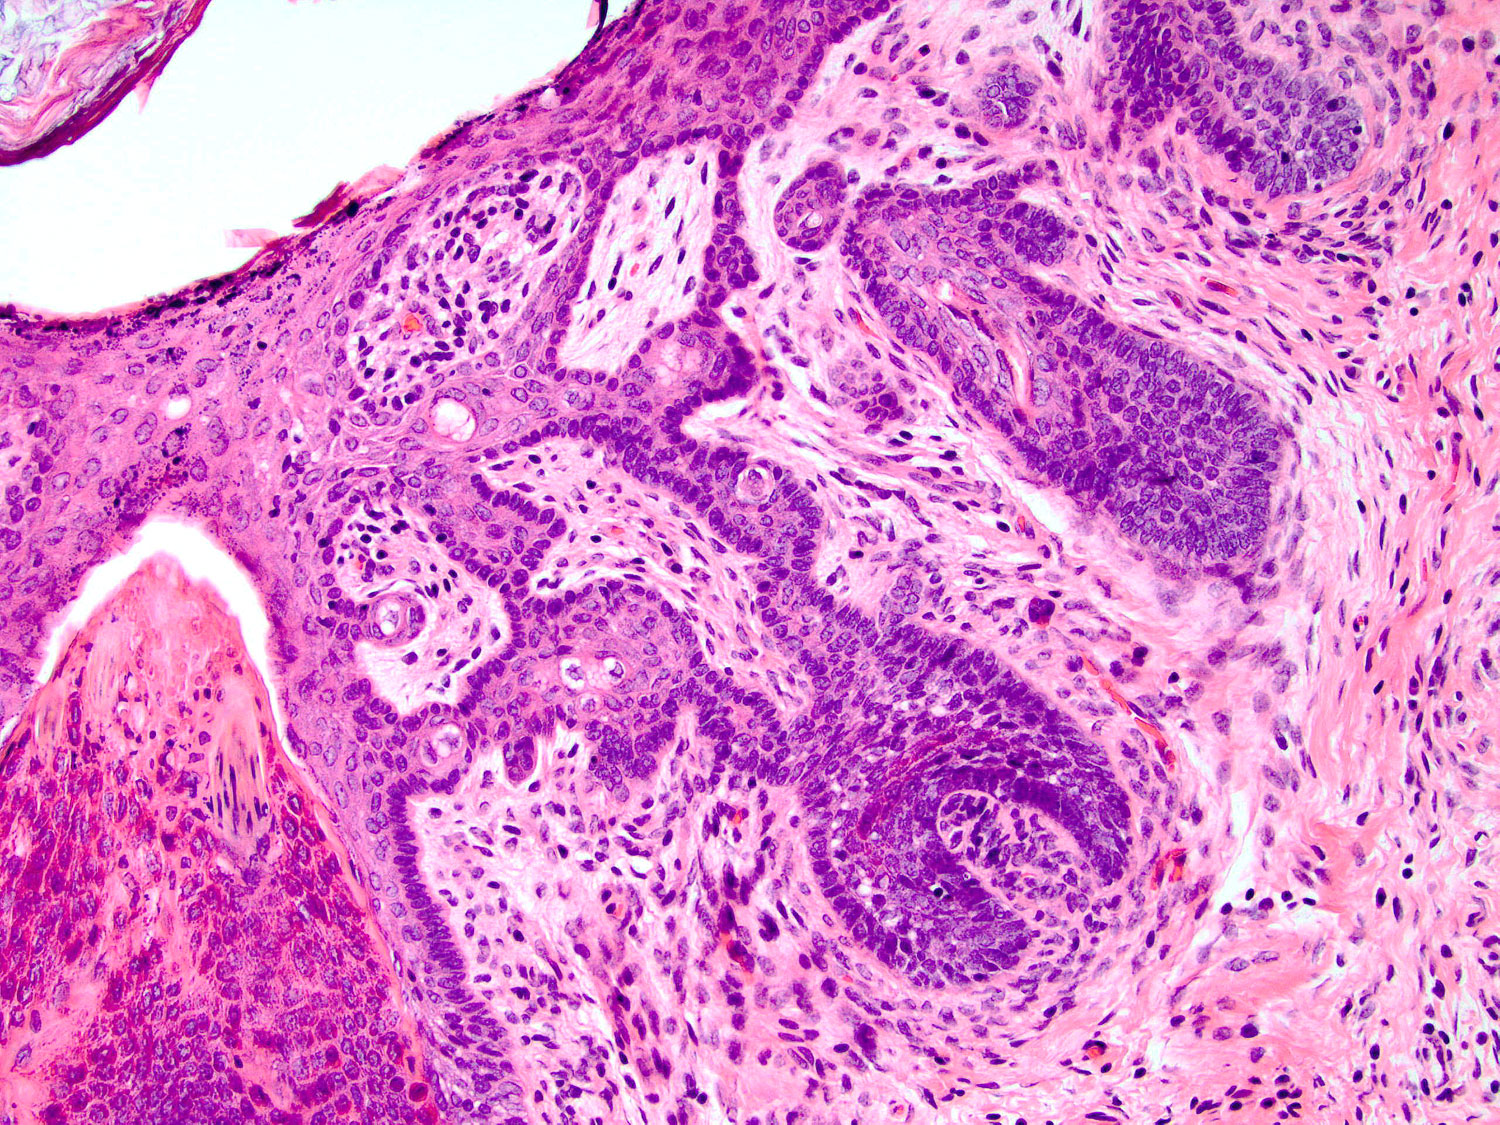

Papillary mesenchymal body

H&E staining (20x objective)